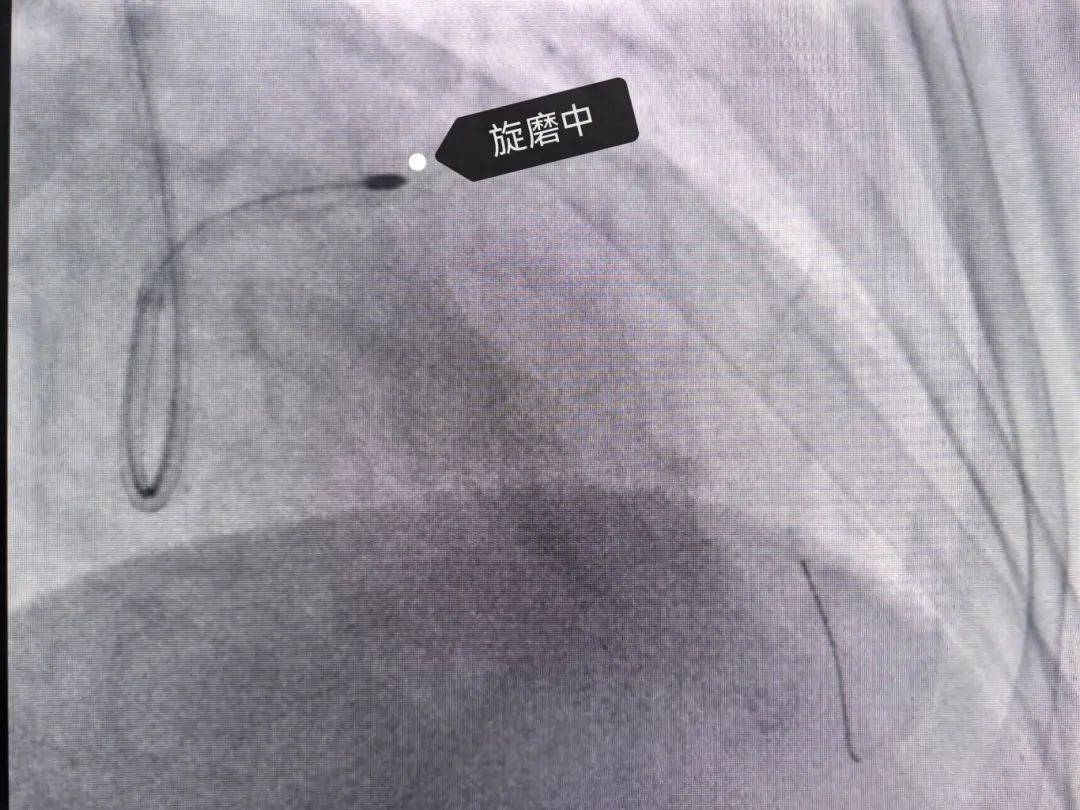

旋磨

冠脉钙化病变的克星冠状动脉内斑块旋磨术

冠状动脉旋磨术介入治疗的护理